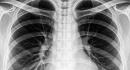

Gujarat Doctors Remove LED Bulb From 1-Year-Olds Windpipe After Weeks Of Illness